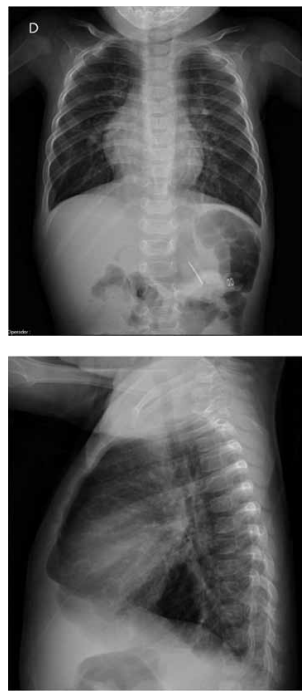

A radiografia de tórax e o eletrocardiograma, a seguir, de

um lactente de 9 meses referem-se a qual cardiopatia

congênita?

(Arquivo pessoal; imagens usadas com autorização)

Com base na radiografia de tórax e no eletrocardiograma

de um lactente de 9 meses, apresentados a seguir, qual

é a malformação cardiovascular mais provável?

(Arquivo pessoal; imagem usada com autorização)